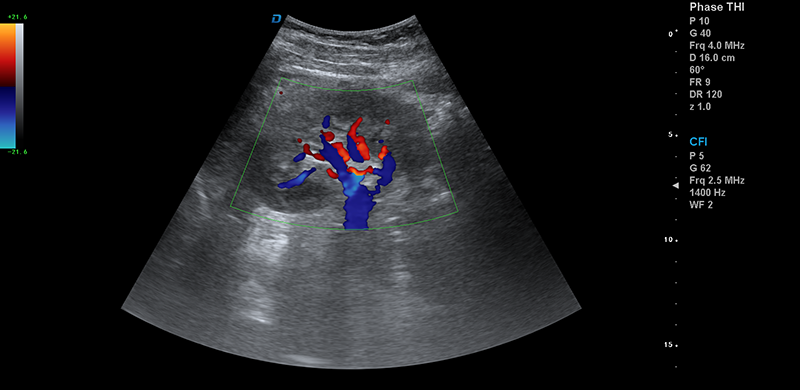

彩超機腎臟血流檢測圖

腎臟血流